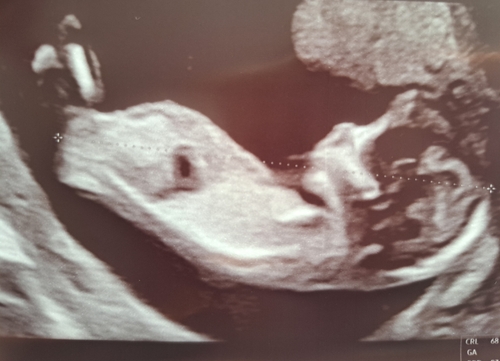

Vroeg meisje met nog een klein beetje tijd om te stijgen naar jongen, al verwacht ik niet meer dat het gaat stijgen, maar je weet nooit!

Ik denk een meisje maar niet heel duidelijk . 🩷

Meisje 🩷

Meisje